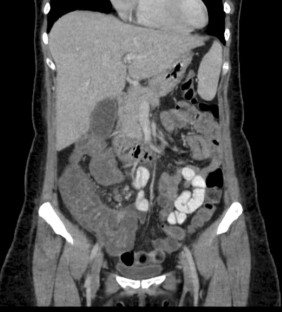

Fig. 1

Fig. 2

Fig. 3